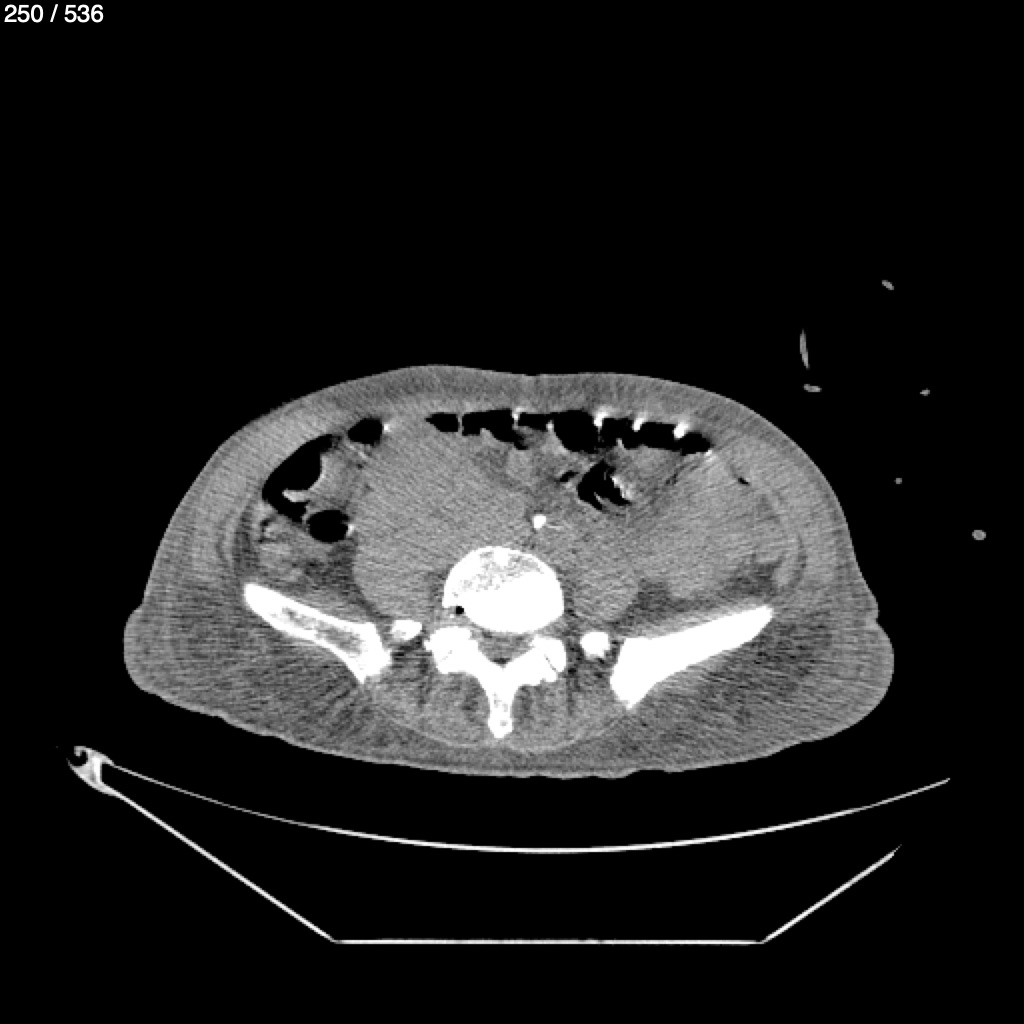

Angel Villalobos Palomeque 73 A - T.C Abdomen Simple